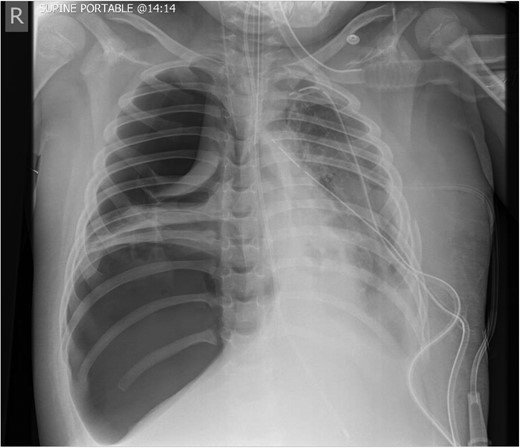

Post operatively, two left sided chest drains were left on free drainage. There were persisting smaller cavities within the left lung. Serial chest radiographs over the next 7 days demonstrated a persisting, increasing left pneumothorax and worsening consolidation of the left lung (Fig. 4). On the 8th post-operative day, the child suffered an acute respiratory deterioration with a reduction in oxygen saturations. The chest radiograph revealed a new right-sided tension pneumothorax which required emergency drainage (Fig. 5).

Worsening appearances of the left pneumothorax despite chest drains in situ.